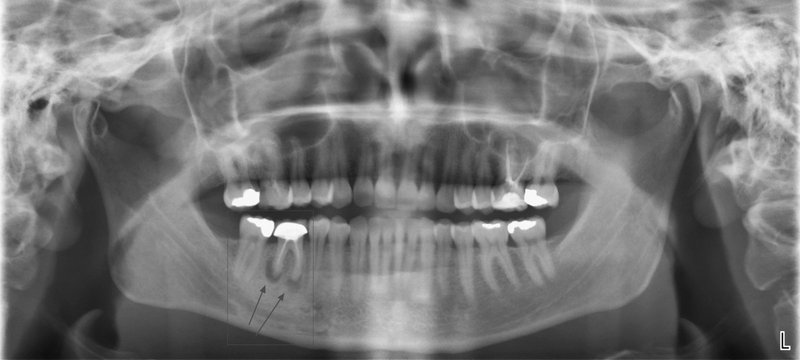

Obr. 1 Pětka a šestka vlevo dole. Oba zuby jsou mrtvé a „otevřené“.

Bakterie tak mohou volně proudit z úst do kosti. Obvyklý vývoj neošetřeného nebo nedokonale ošetřeného kazu je prostup bakterií do prostoru dřeňové dutiny. Počáteční dlouhodobá citlivost na chlad a sladké se změní v pulzující špatně ztišitelnou bolest, která budí pacienta ze spaní. Už v této chvíli je vlastně pozdě a zubní lékař by měl ošetřit kořenové kanálky a zamezit bakteriím v šíření hlouběji do zubu. Nestane-li se tak, šíří se infekce kořenovými kanálky dál hlouběji směrem do čelistní kosti. V tuto chvíli se dostaví výrazná bolest na skus. A jsme opět na křižovatce. Tělo buď zánět převede do chronicity a vytvoří se obávaný váček prostupující všechny internetové diskuze pod zubařskými články, nebo infekce pokračuje akutně dál. Člověka sužují kruté bolesti z rozvíjejícího se abscesu, což není nic jiného, než jezero hnisu. Absces se může provalit do úst, což je sice krajně nechutné, ale přinese to aspoň částečnou úlevu. Pokud se ale hnisavý zánět šíří štěrbinovitými anatomickými komunikacemi dál, nastává problém. Infekce může v závislosti na příčinném zubu směřovat do oka, do mozku, do plic nebo srdce. Vůbec nejhorší jsou extrémně rychle probíhající infekce, kdy se hnis ani nestihne vytvořit a člověk navzdory antibiotikům a intenzivní péči umírá na selhání orgánů při sepsi nebo i udušení z otoku dýchacích cest. Léčba takovýchto stavů je i dnes velmi obtížná a často vyžaduje rozsáhlé chirurgické zákroky.